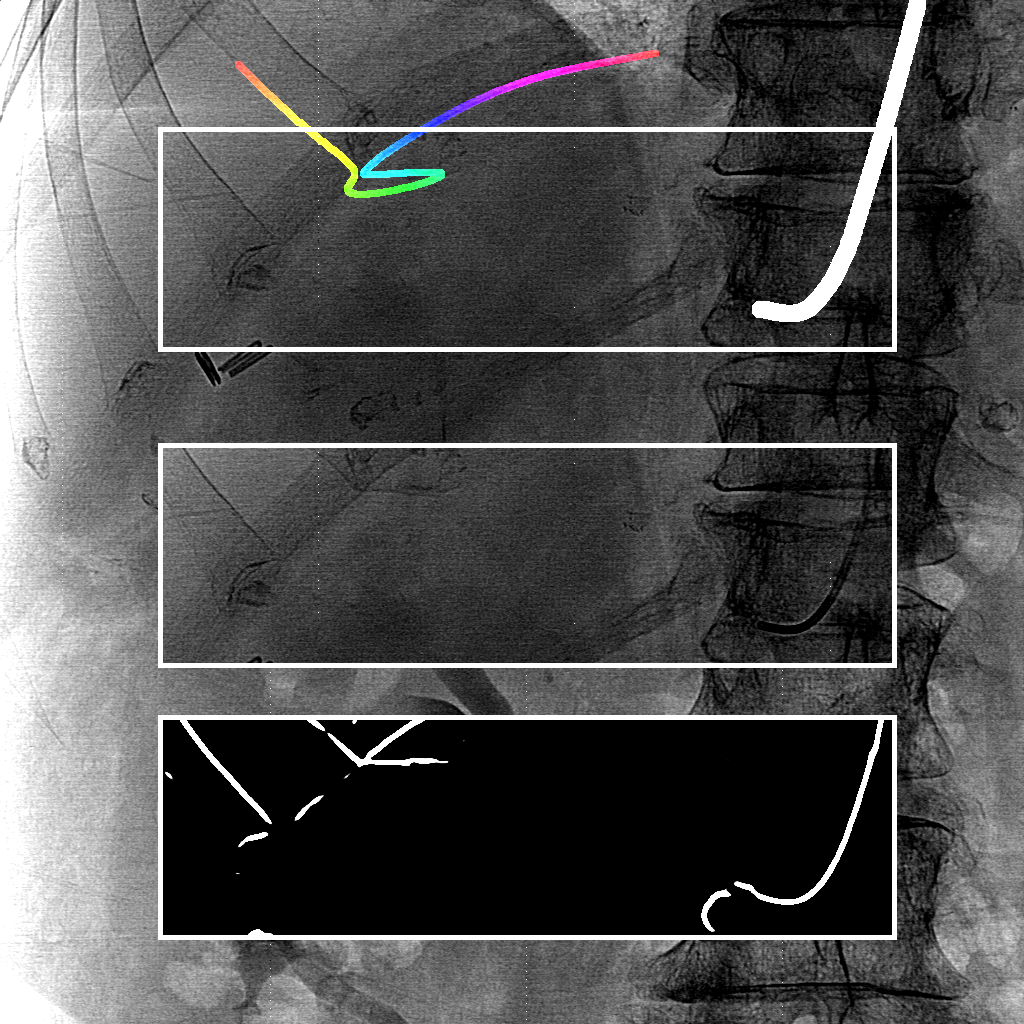

We evaluate using the tip distance error (i.e. the distance between the annotated catheter tip and the tip of the segmented catheter), and the average distance between the manually segmented catheter and the automatically segmented catheter. Figure 3 shows the tip and catheter distances results. We compute the precision of the tip between consecutive frames. The median, average, minimum and maximum of the standard deviation per sequence of the tip distance error are respectively 0.7 mm, 4.9 mm, 0.1 mm and 55.7 mm. Five examples of segmentation are shown in Figure 4. In the third frame, the segmentation is going too far and follows part of the vertebrae. The fourth frame misses the proximal part of the catheter. The last frame is the only sequence with significant false positives. It is less noisy because it has been acquired with higher radiation dose. The neural network was not trained for such sequence.